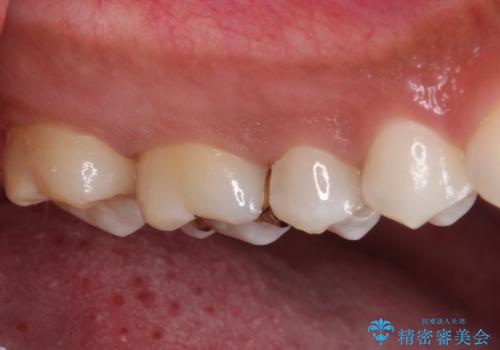

ゴールドインレーは銀歯のインレーやセラミックインレーと比べ、「技工操作の精度が高く、適合が著しく良い」というメリットがあります。特に上の奥歯は歯科医師の操作が行いにくいため、「適合の良さ」は再治療のリスクを防ぐ上でとても重要な要素となります。

上の奥歯は金属色が見えることもないため、審美的な問題は全くありません。

咬み心地はとても良好で、全く違和感がなく、患者様には大変満足していただきました。